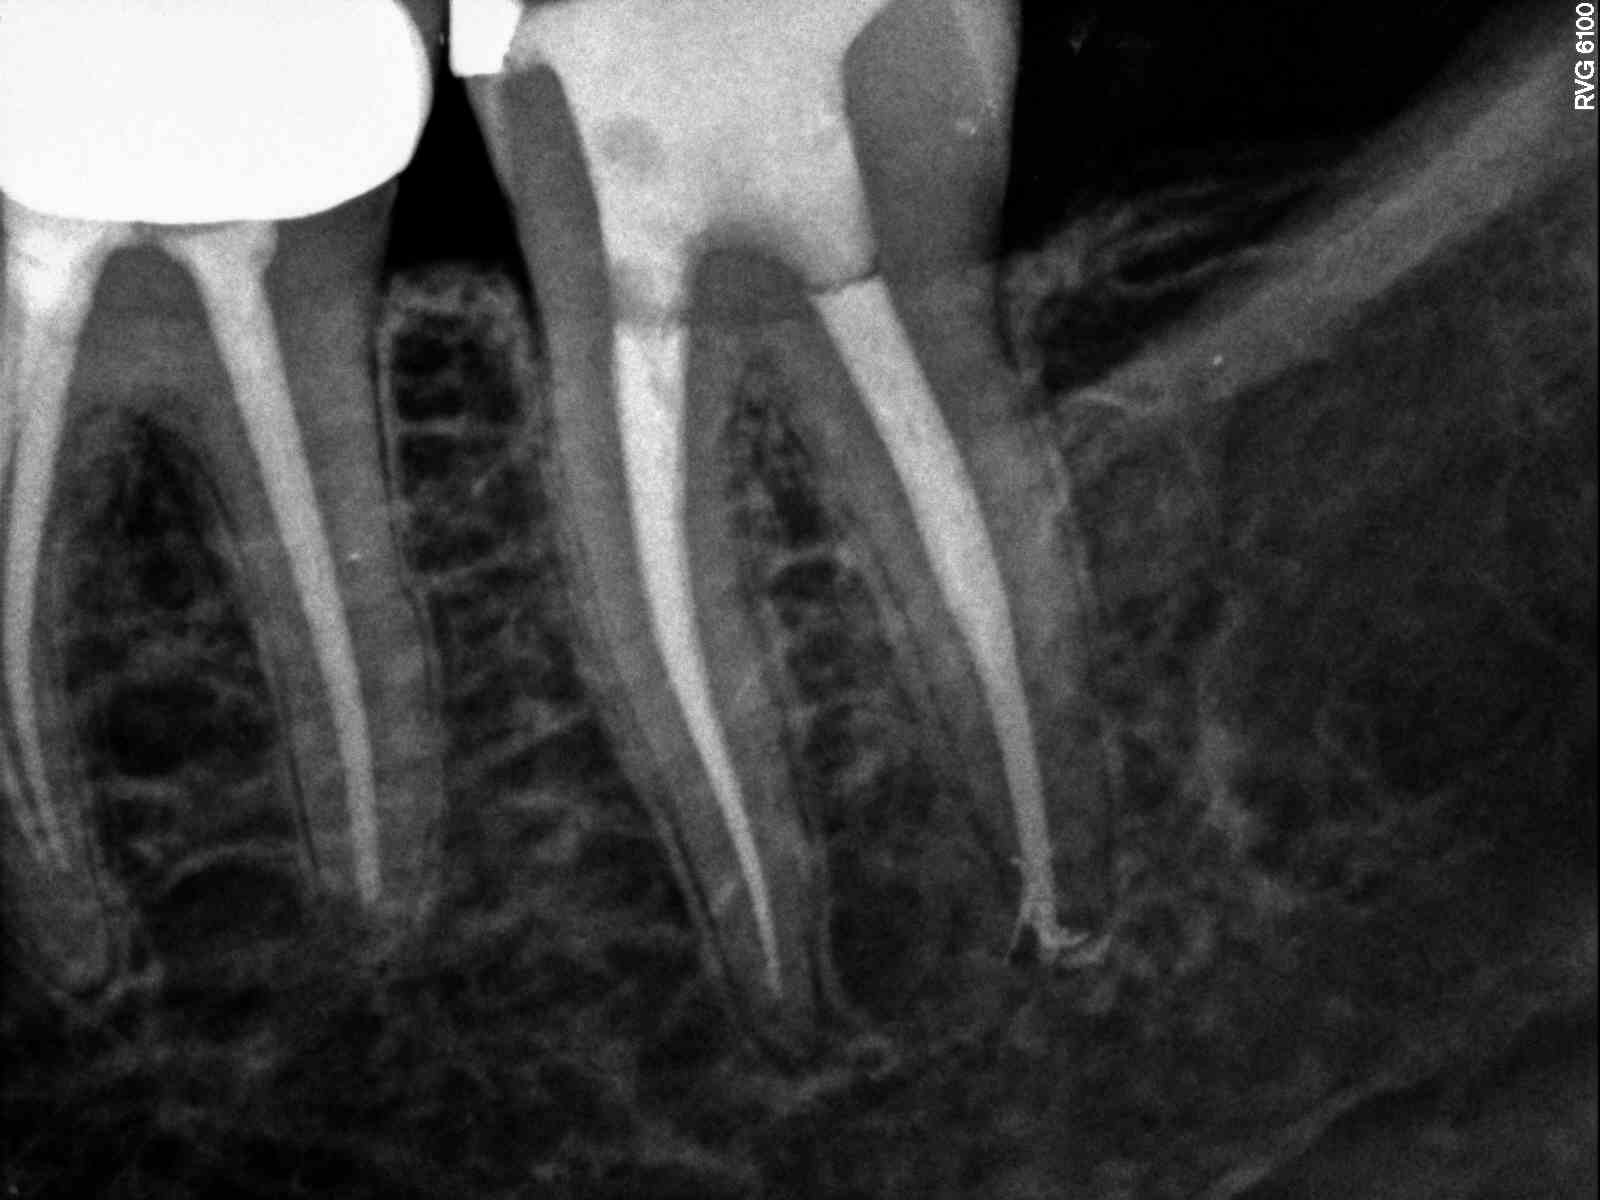

Small piece white path file separated past apex in distal. Normal anatomy

| Can see file in distal canal heading mesially at apex |